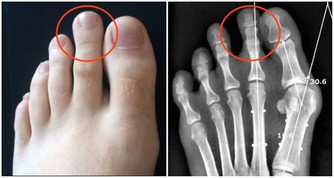

蛀牙蛀牙是口腔疾病中發病率最高的幾種疾病之一,也是許多人人生中第一次去看牙醫的原因。

口腔裡的細菌吃了食物殘渣之後,會產生酸類物質,長此以往,酸會漸漸腐蝕牙齒硬組織,形成齲齒。

牙齒的表面光滑,也容易清理到,但牙縫就不一樣了,這裡的細菌和殘渣很難被清除。

有時候發現牙齒上有黑縫時,就說明蛀牙可能已經發展很久了。

不一定。蛀牙有時很難自己發現。除了前面提到牙縫裡隱匿的蛀牙之外,

還有一些蛀牙長在大牙面上的窩溝裡,表面上看起來只有小小一個洞,非常不引人注意。

但實際上,蛀牙露出來的部分只是冰山一角,在牙齒深部可能已經醞釀出巨大的損傷了。